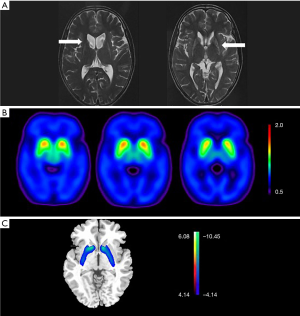

Both magnetic resonance imaging (MRI) and PET scanning were applied due to the parkinsonism phenotype of the patient. PET imaging and image processing were performed using previously reported methods (1), in which the network expression in fluorodeoxyglucose F 18 (18F-FDG) PET scanning was represented with a transformed Z score by using the subject scores of healthy controls in a Chinese cohort.

Volume loss and hyperintense signals of the bilateral basal nuclei on T2 were observed in the MRI (Figure 1A). 18F-dihydrotetrabenazine (DTBZ) PET scanning showed symmetrical vesicular-monoamine-transporter-type 2 (VMAT2) binding reductions in the bilateral striatum (Figure 1B), and the posterior putamen was the most affected structure, followed by the anterior putamen and the caudate. This was a feature shared by PD and HD on VMAT2 PET (2,3). While increased striatal metabolism is one of the core characteristics found in the metabolic brain network of PD patients (4), in the case of our patient, the processed 18F-FDG PET images showed obvious hypometabolism of the bilateral caudate and putamen (Figure 1C), which distinguished the patient’s condition from PD. Although no obvious decrease in cortical metabolism was found, the pattern found in network analysis was observed to be closer to that of adult-onset HD (AOHD), which is characterized by marked striatal hypometabolism and relative decreases in the metabolism of the temporal cortex (5).

PET scans have long been used to evaluate patients with JOHD; however, to our knowledge, this case is the first dual-tracer PET study of JOHD to be reported. Although our patient’s patterns on 18F-DTBZ and 18F-FDG PET scans were found to be closer to that of AOHD, the difference in glucose brain metabolism between JOHD and AOHD assisted with differential diagnosis. While decreased metabolism of the temporal cortex is a typical feature of AOHD, it is not observed in JOHD. In fact, recent MRI and postmortem studies (6,7) in JOHD have reported a selective and severe loss of volume in the striatum with preserved cerebral cortex volume. In contrast to AOHD, JOHD exhibits a unique lack of cortical involvement, which was supported by the almost normal metabolism of the cortex in our patient.